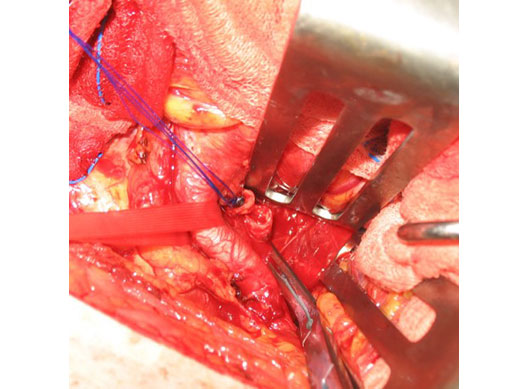

Περίπτωση 4

Άνδρας ασθενής 73 ετών με προηγούμενη (προ 14 ετών) ανοικτή χειρουργική αποκατάσταση ανευρύσματος κοιλιακής αορτής παρουσιάζει ανευρύσματα κοινών λαγονίων άμφω δεξιά 5,2 εκατοστών και αριστερά 5,5 εκατοστών και επιπρόσθετα απόφραξη της αριστερής έσω λαγονίου αρτηρίας

Αντιμετωπίστηκε με υβριδική επέμβαση (ανοιχτή και ενδαγγειακή) με την χειρουργική μετάθεση της δεξιάς έσω λαγονίου αρτηρίας περιφερικότερα στην έξω λαγόνιο (εξωπεριτοναϊκή προσπέλαση) και την τοποθέτηση μοσχεύματος τύπου Excluder, ώστε να διατηρηθεί η